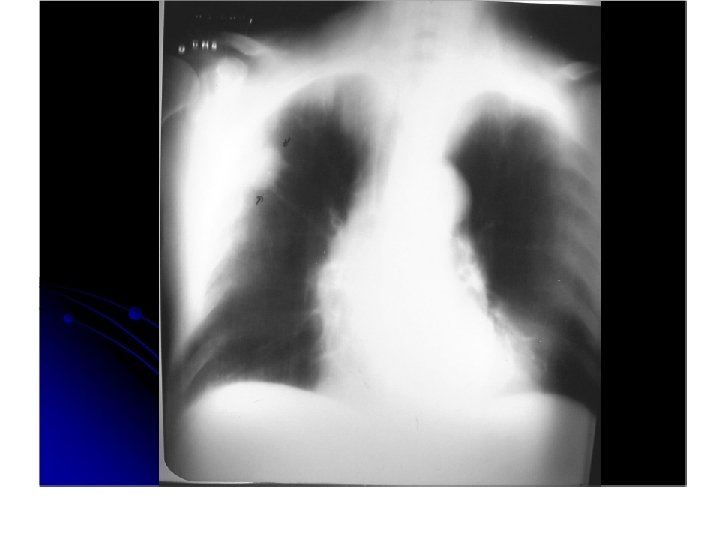

Carcinoma de celulas pequeñas • Altamente asociado a tabaquismo 10 -15% de cancer de pulmón. • Sospechar ante un hilio pulmonar aumentado de tamaño. • sin tratamiento, la sobrevida es de 2 -4 meses. • Mas común de localización central.

Enfisema centrolobulillar. Infiltrados intersticiales. Masa parahiliar izqueirda.